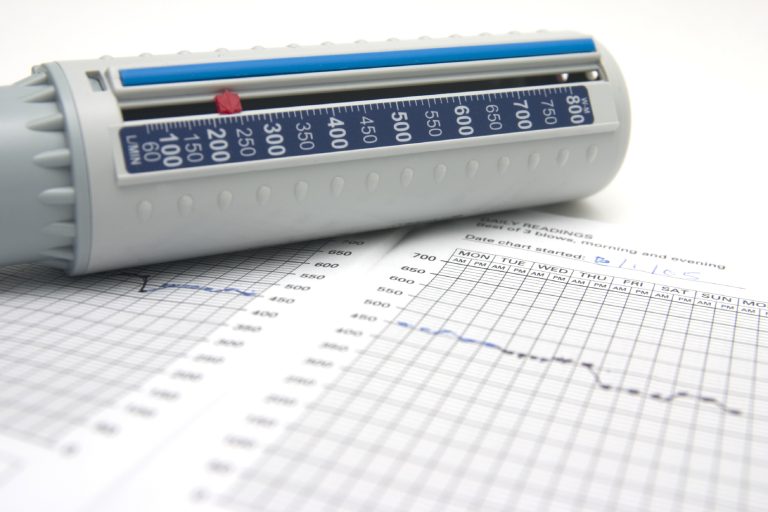

- Schnelle Einschätzung anhand vorhandener Befunde (CT/Röntgenbildern/Arztbrief/Mikrobiologie)

- Befunden und Bildgebung (Röntgen/CT/MRT)

Unterlagen

Wir möchten, dass Sie mit unserem Therapieverlauf zufrieden sind. Bitte senden Sie uns vorhandene Befunde: CT(Thorax), Arztbriefe, OP-Berichte, ggfs. mikrobiologische Ergebnisse und Ihre Medikamentenliste

- knöcherne Situation (Fraktur/Teilfraktur/Quer-/Längsfraktur)

- retrosternale Anatomie /Bypässe, Aorta, Verwachsungen

- CT-Thorax / CT-Bericht / Röntgenbilder